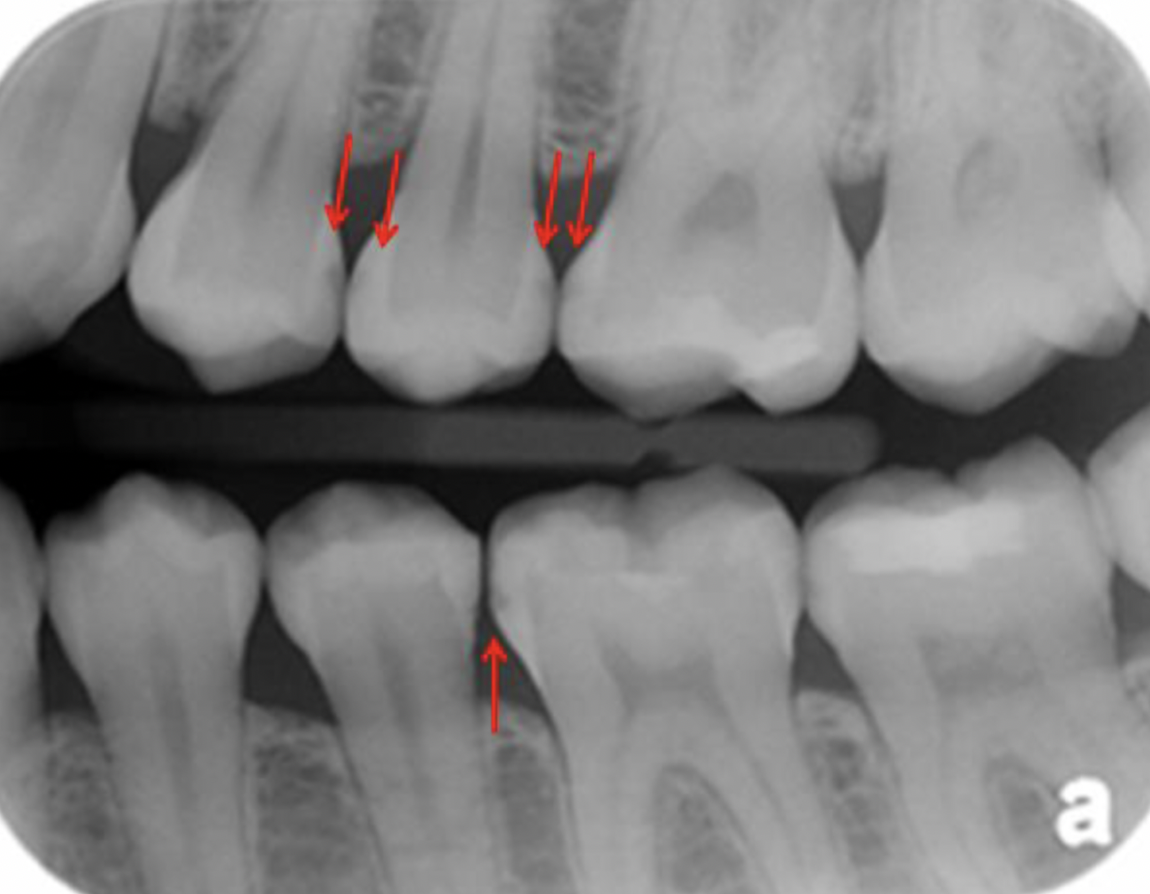

Q

Classify the caries

A

moderate caries (MC)